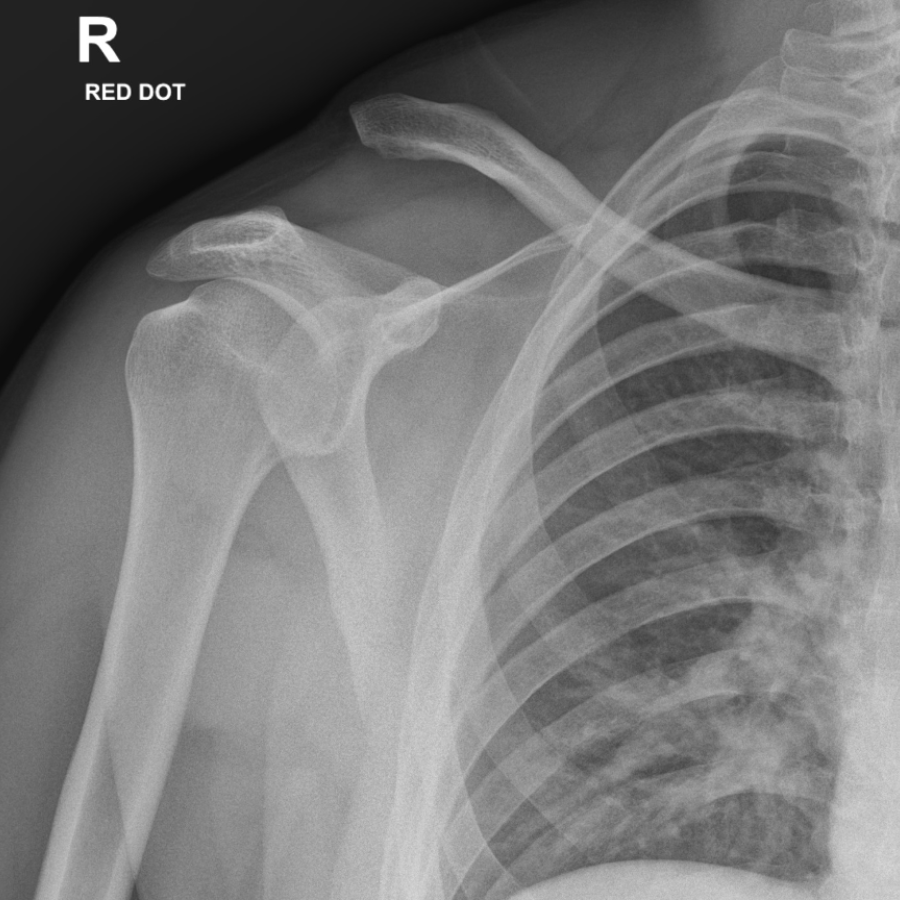

Acromioclavicular Joint Injuries

The acromioclavicular joint is a small joint between the outer end of the collar bone (clavicle) and the top of the shoulder blade (scapula). The joint is commonly injured by a fall on to the point of the shoulder. This can destabilise the joint and tear the ligaments which hold the joint in place. This allows the outer end of the collar bone to become prominent beneath the skin which can be seen and felt as a step or bump.

When should surgery be considered for an acromioclavicular joint injury?

Treatment with surgery is considered for more severe injuries to the joint and in patients with physically demanding occupations or who are keen sportsmen or women. The damaged ligaments can be reconstructed soon after the injury and the clavicle held back in place using a specially designed suture that holds the clavicle in place.